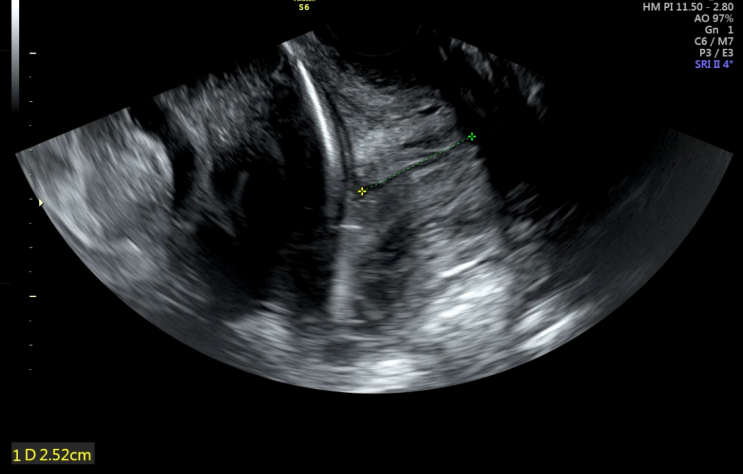

쌍둥이 32주 검진 기록 / 붓기와의 전쟁 시작

2022.09.13(화) 연휴를 끝내고 32주 정기검진을 다녀왔다 퇴원 후 이틀정도 배뭉침도 심했고 붓기도 많이 ...